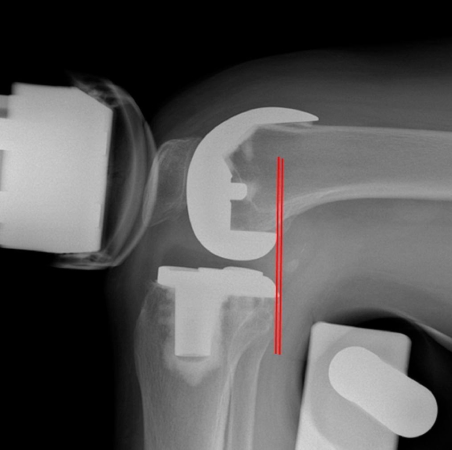

Los diseños estabilizados posteriormente y ultracongruentes son dos ejemplos comunes de prótesis de artroplastia total de rodilla (ATR) que sustituyen el ligamento cruzado posterior. Hay una falta de evidencia con respecto a las diferencias de percepción articular entre la ATR ultracongruente y estabilizada posteriormente. El propósito de este estudio fue comparar la estabilidad, función y percepción articular de la rodilla postoperatoria entre la ATR ultracongruente y la estabilizada posterior en los mismos pacientes para determinar si había una diferencia basada en el diseño.

Este ensayo controlado aleatorio prospectivo incluyó a 50 pacientes que se sometieron a una ATR bilateral el mismo día utilizando por persona implantes estabilizados en la parte posterior (Zimmer Biomet) en una rodilla (grupo estabilizado en la parte posterior) e implantes ultracongruentes en la otra rodilla (grupo ultracongruente).

A los 2 años del posoperatorio, se evaluó a los pacientes para determinar la estabilidad, función y percepción articular de la rodilla. Se compararon la estabilidad anteroposterior de la rodilla estática posoperatoria y el retroceso femoral.

Ambos grupos tenían una percepción articular similar 2 años después de la operación, con diferencias obvias en la generación de ruido y más laxitud sagital con menos retroceso femoral en el grupo ultracongruente.